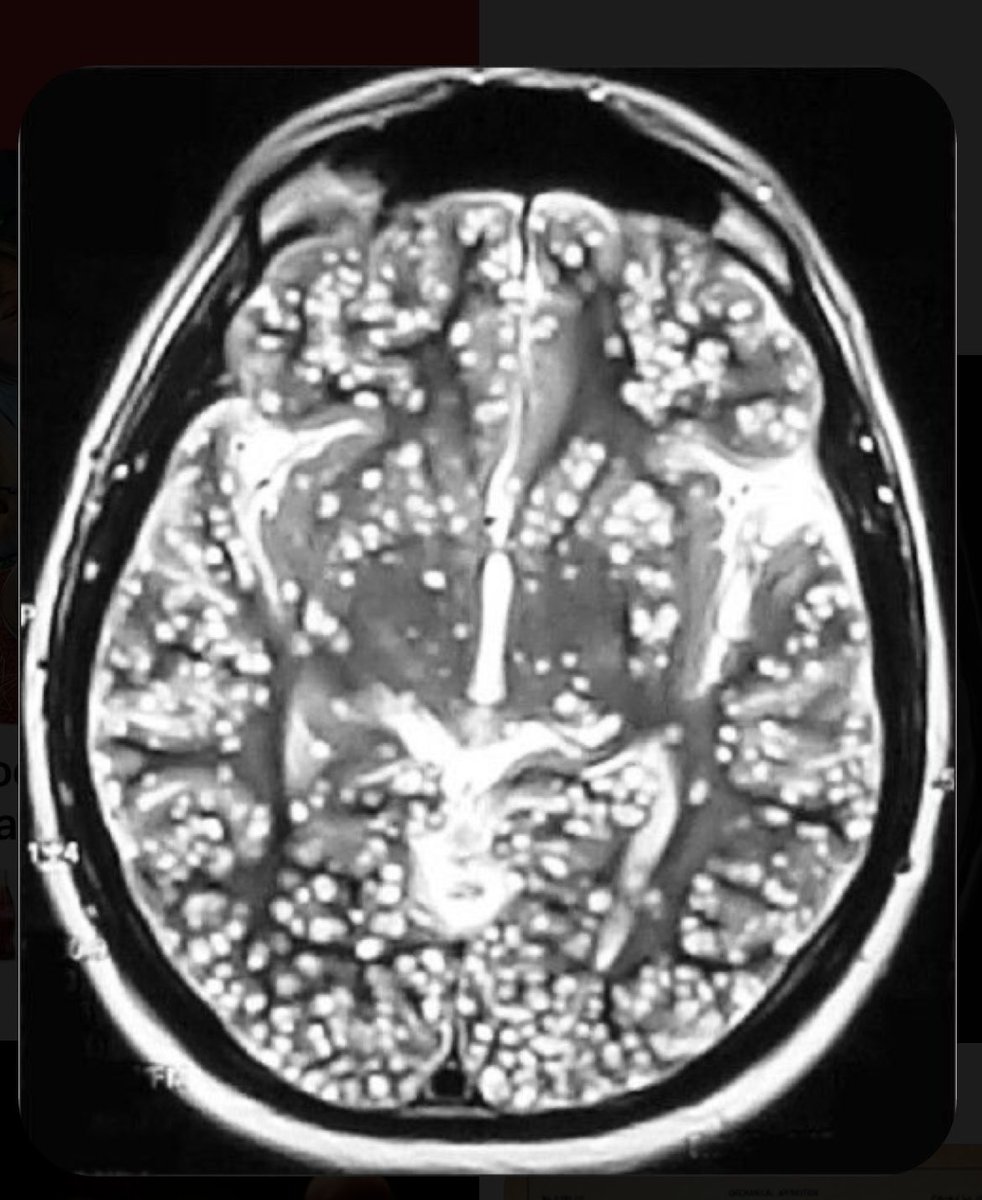

Фото Червей В Голове

Фото Червей В Голове 112 фотографий